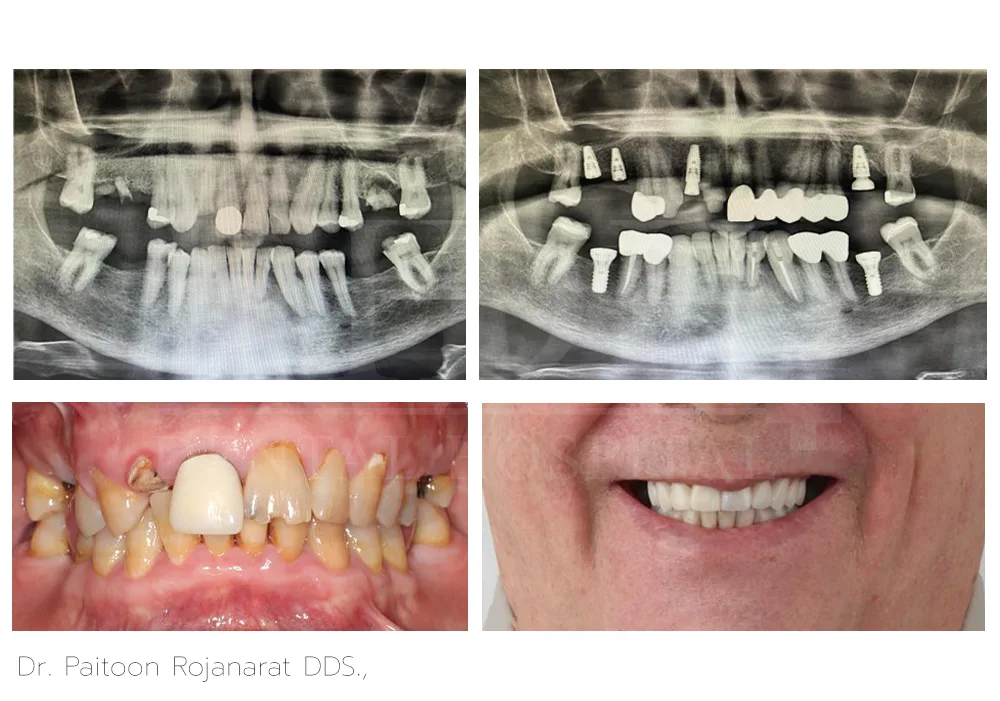

Dr. Paitoon Rojanarat DDS.,

Dr. Paitoon Rojanarat, DDS, is a dentist specializing on prosthodontics and esthetic dentistry that includes crowns, bridges, dental implants, veneers, and teeth whitening. With his highly-skilled and qualified expertise, he crafts custom-made fixed hybrid bridges over implants and dentures over implants designed for a natural appearance and a comfortable fit.